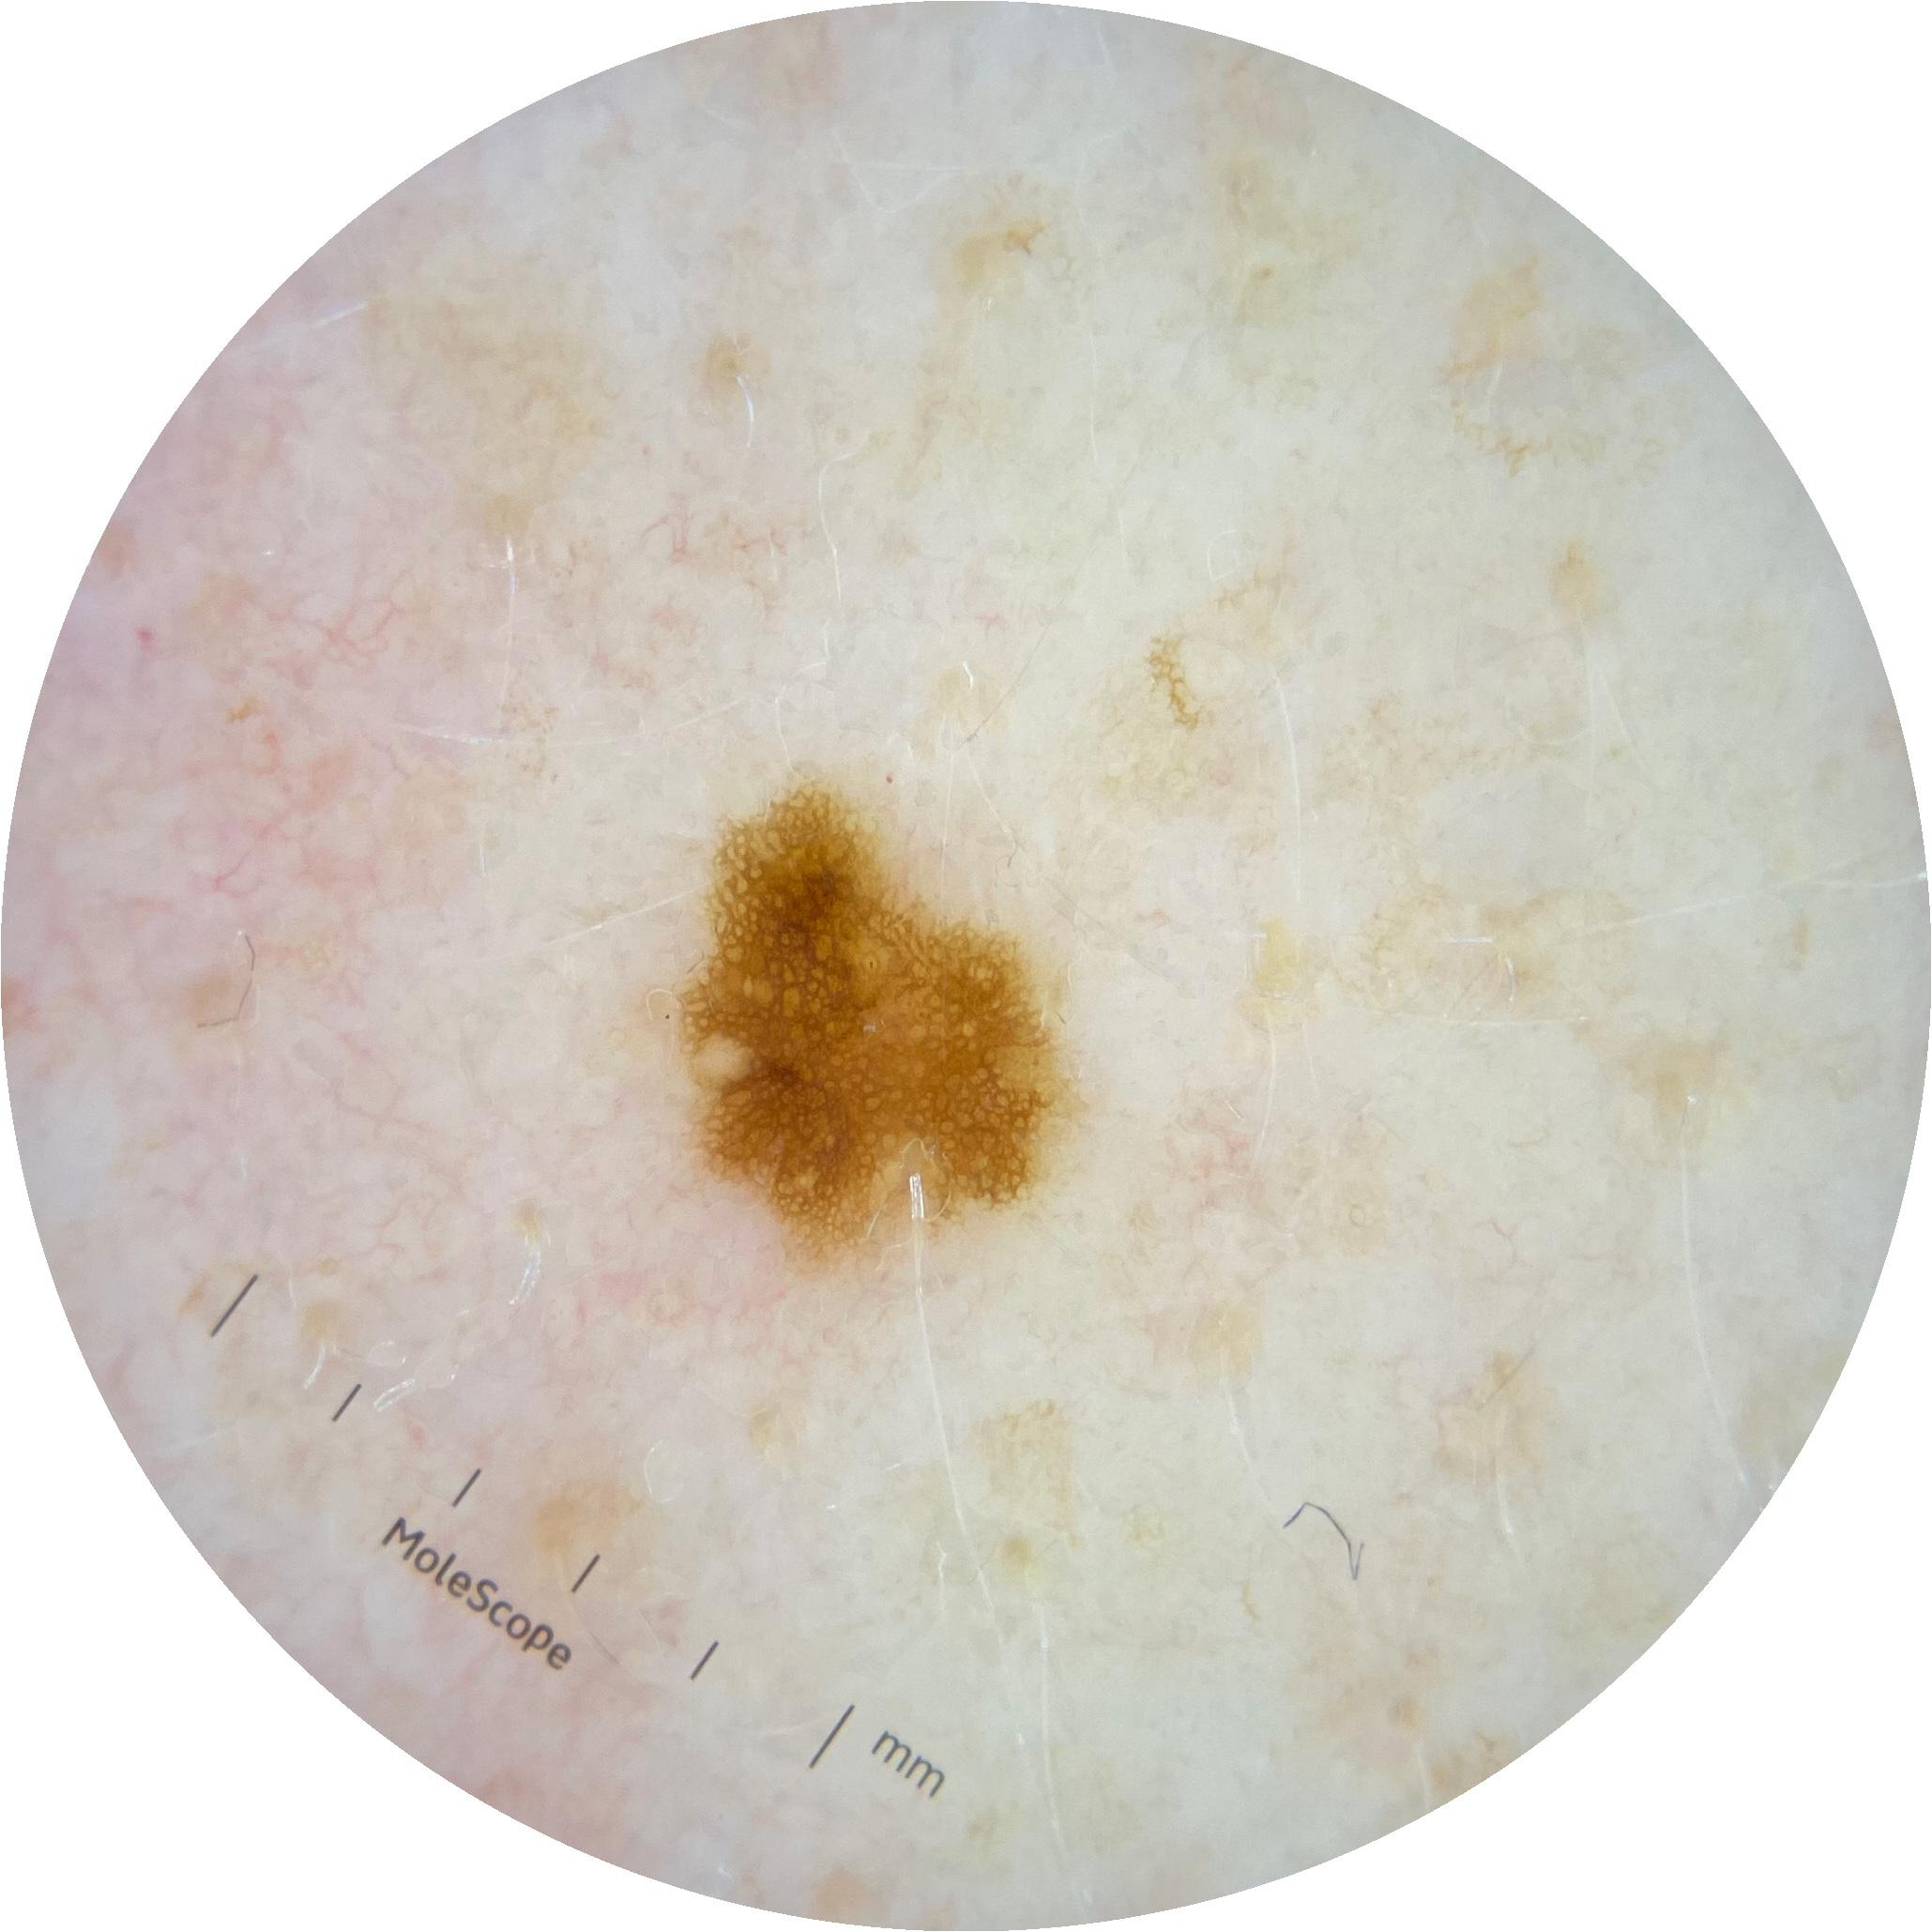

ISIC_2261268

Information

2061 x 2061

MEL-SELF Trial, https://www.sydney.edu.au/medicine-health/our-research/research-centres/melself-project.html

Clinical

Field Value

acquisition_day 307

age_approx 50

anatom_site_1 Trunk

anatom_site_2 Posterior trunk

anatom_site_general posterior torso

diagnosis_1 Benign

diagnosis_confirm_type single image expert consensus

image_type dermoscopic